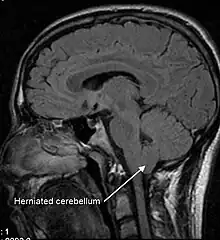

Low CSF volume can cause the cerebellar tonsil position to descend, which can be mistaken for Chiari malformation; however when the CSF leak is repaired the tonsil position often returns to normal (as seen in upright MRI) in this "pseudo-Chiari" condition.[57] A further, albeit rare, complication of CSF leak is transient quadriplegia due to a sudden and significant loss of CSF. This loss results in hindbrain herniation and causes major compression of the upper cervical spinal cord. The quadriplegia dissipates once the patient lies supine.[58] An extremely rare complication of sCSFL is third nerve palsy, where the ability to move one's eyes becomes difficult and interrupted due to compression of the third cranial nerve.[59]

An untreated CSF leak can result in coma or death as late stage findings as the brainstem herniates through the skull base or foramen magnum .[35][33]